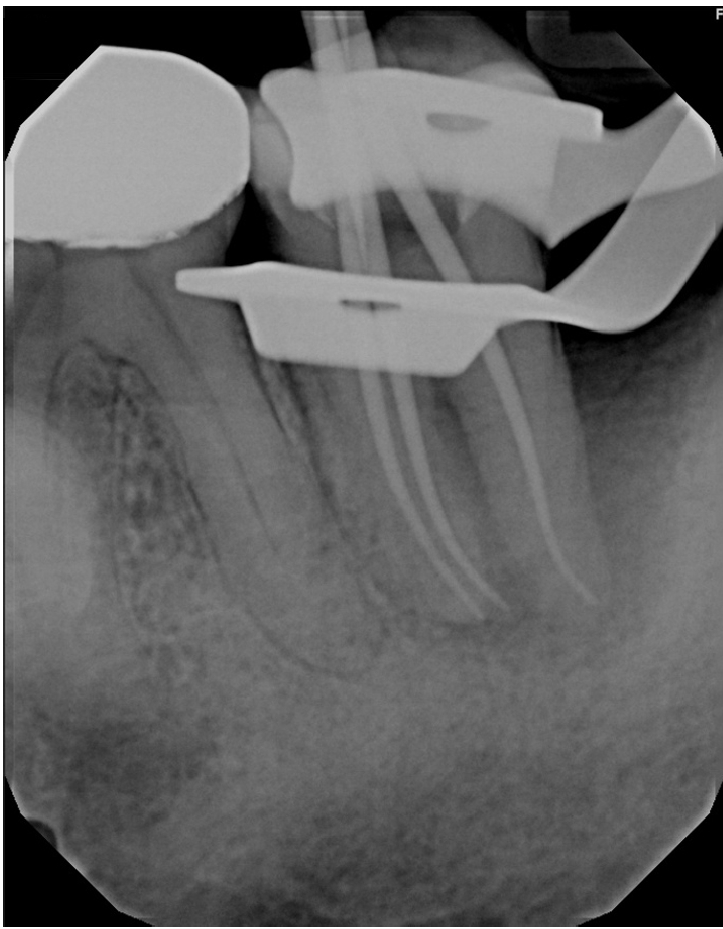

Working lengths were determined using an electronic apex locator (RootZX; J Morita, Kyoto, Japan) and confirmed with a periapical radiograph, which also showed a radiopaque fragment consistent with a cemental tear (Figure 2). The chamber was flooded with 5% sodium hypochlorite, and the canals were instrumented using size 8, 10, 15, and 20 K files, followed by a 25/.07 Primary Wave One Gold (Dentsply Sirona, Charlotte, NC, USA) reciprocating file. Irrigation was performed with 12 mL of 5% sodium hypochlorite with ultrasonic activation for 30 seconds per canal. Calcium hydroxide was placed as an intracanal medicament with a lentulo spiral, and the tooth was temporized with a sterile sponge and Cavit (3M ESPE, St. Paul, MN, USA). The patient was informed to return in 2 weeks for completion of the root canal.

Figure 2.

Working length radiograph showing radiopaque fragment consistent with a cemental tear along distal root (red arrow).

rde-2025-50-e31f2.jpg